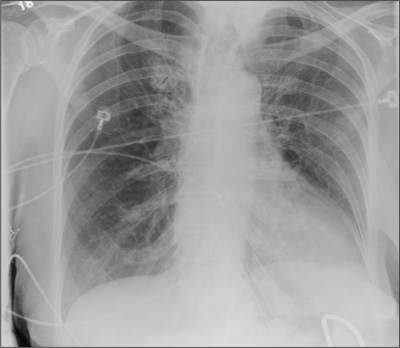

The radiograph shows the lungs overall to be clear. There are some slight increased markings, perhaps suggestive of mild congestion, but no infiltrate or consolidation.

Of note is a small nodule within the middle portion of the left upper lobe that requires monitoring and further workup. Also, although it is incompletely imaged, there appears to be a fracture of the right humeral neck.

Additional imaging confirmed the fracture. Orthopedic consultation was obtained.